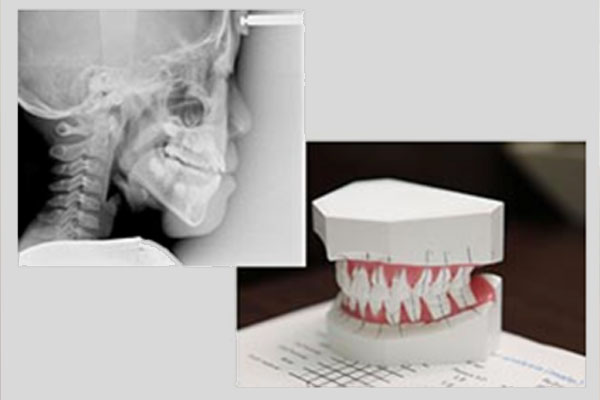

より正確な治療を行うために、虫歯や歯周病の確認だけでなく、歯科用CTやセファロを用いて様々な検査を行い分析します。

精密検査の結果をもとに、矯正専門の歯科医師が診断を行います。

治療計画を立案後、担当医が患者さまに分かりやすく、丁寧にご説明いたします。